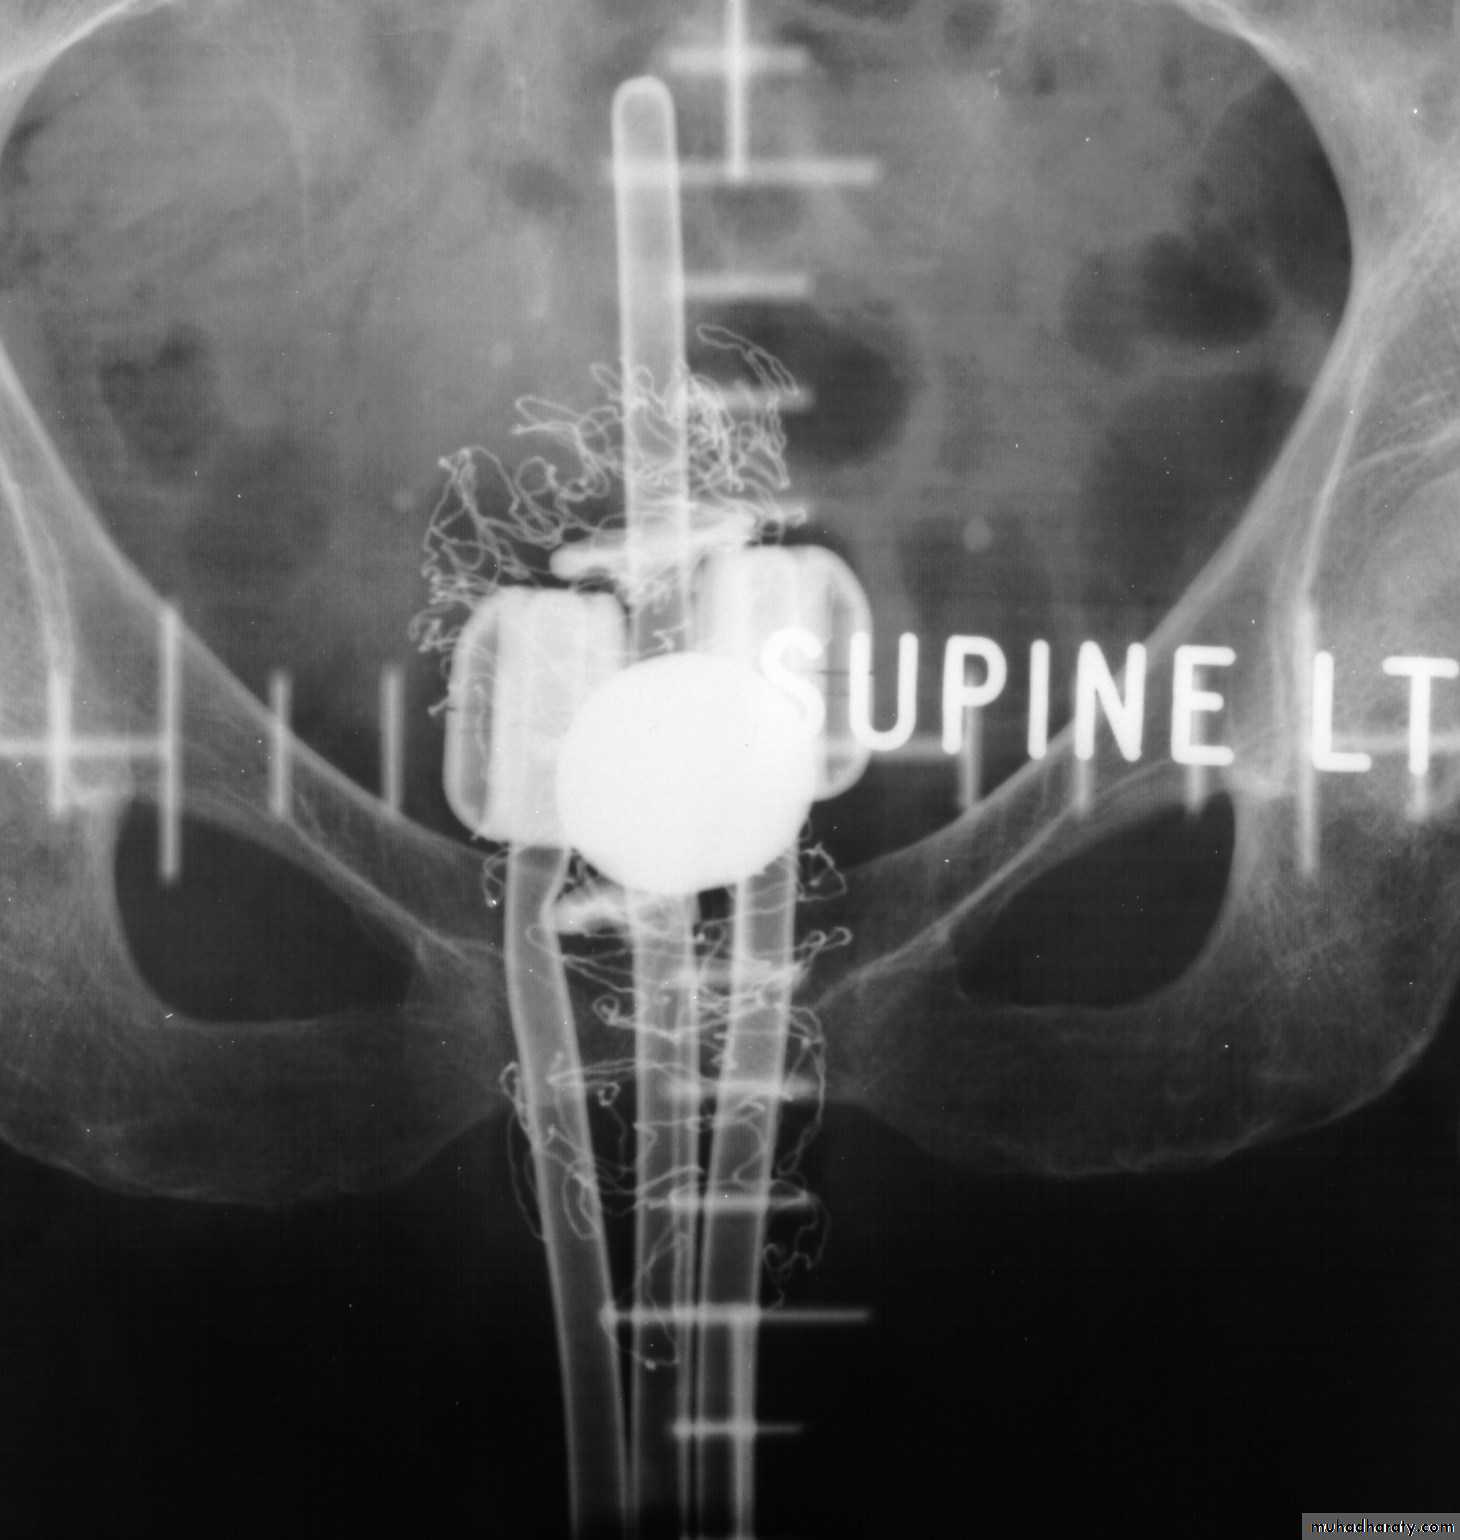

Intracavitary treatments

• 137Cs (Ceasium)• Cervix & vagina using afterloaded source trains in plastic applicators.

• 192Ir (Iridium)

• The Microselectron - small, active source driven into applicatorsSurface applicators